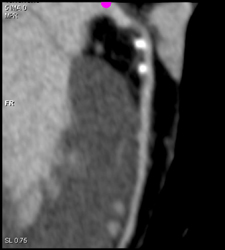

Left Main Arises Off Right Coronary Artery